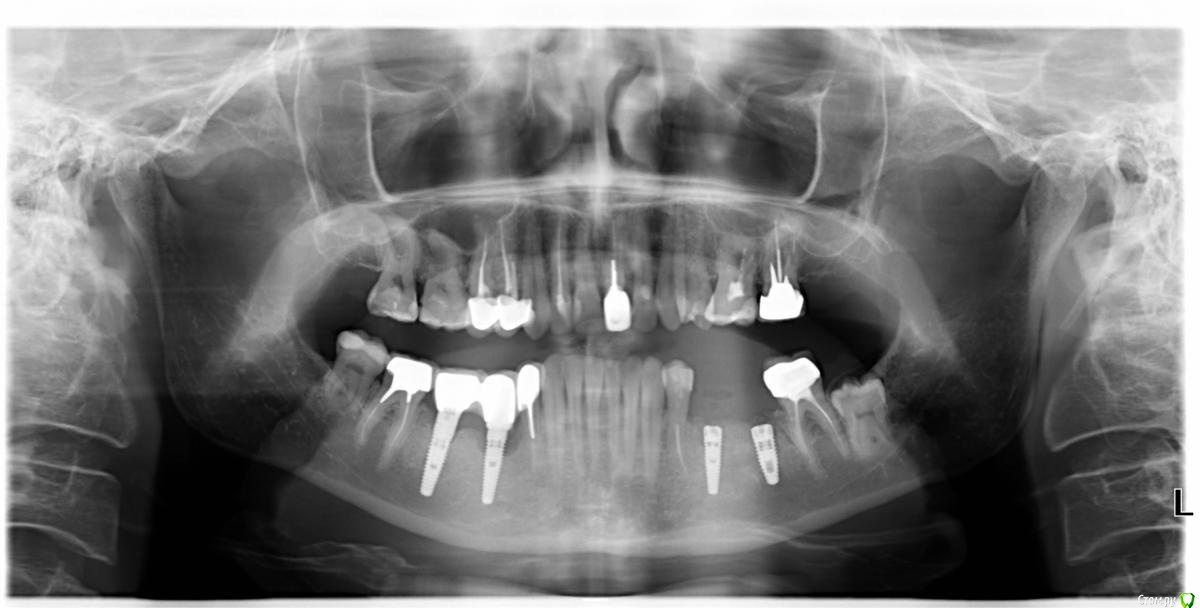

k.t.m. Опубликовано 12 сентября, 2015 Поделиться Опубликовано 12 сентября, 2015 Мембрана коллагеновая была,нет пинов на оптг?викрил есть викрил...)4.5 ваша работа,с чем связываете резорбцию? Ссылка на комментарий

Глеб Митрофанов Опубликовано 12 сентября, 2015 Автор Поделиться Опубликовано 12 сентября, 2015 Мембрана коллагеновая была,нет пинов на оптг?викрил есть викрил...)4.5 ваша работа,с чем связываете резорбцию? Был биогайд , поверх А-PRF , мембрана фиксирована швами , правая сторона не моя Ссылка на комментарий

колесников Опубликовано 12 сентября, 2015 Поделиться Опубликовано 12 сентября, 2015 4.5 ваша работа,с чем связываете резорбцию?С нобелем Ссылка на комментарий

Mane Опубликовано 12 сентября, 2015 Поделиться Опубликовано 12 сентября, 2015 Двойная работа.В итоге все равно нкр.разрез дистальный мне не понравился - от шейки зуба воротник остался дальше оторвалось?6-й поставил слишком дистально 1 Ссылка на комментарий

DoctorN Опубликовано 15 сентября, 2015 Поделиться Опубликовано 15 сентября, 2015 ,с чем связываете резорбцию?С нобелемс Mis , с Ankylos -сами продолжите списокankilos периимплантит.bmpMis периимплантит.bmp 1 Ссылка на комментарий

колесников Опубликовано 15 сентября, 2015 Поделиться Опубликовано 15 сентября, 2015 с Mis , с Ankylos -сами продолжите списокНе соглашусь . У вас тут огрехи в протезировании. Так перепоганить анкилос надо ещё суметь. Да и на мисе целый букет. 3.75 на моляр(!),там же: изначально шейка импланта на 2мм выше гребня. +консоль. Чегоже тут ждать?конечно перегруза. односторонняя краевая резорбция на снимке-это перегруз Rh подтверждённый. Имплант тут непричём. 1 Ссылка на комментарий

DoctorN Опубликовано 16 сентября, 2015 Поделиться Опубликовано 16 сентября, 2015 Не соглашусь . У вас тут огрехи в протезировании. Так перепоганить анкилос надо ещё суметь. Да и на мисе целый букет. 3.75 на моляр(!),там же: изначально шейка импланта на 2мм выше гребня. +консоль. Чегоже тут ждать?конечно перегруза. односторонняя краевая резорбция на снимке-это перегруз Rh подтверждённый. Имплант тут непричём.импланты и протезирование -не мое.консоль-не соглашусь,на replace "почему то " у меня работает. почему то 3.5 работаетконсоль.bmp Ссылка на комментарий

IvanK Опубликовано 16 сентября, 2015 Поделиться Опубликовано 16 сентября, 2015 3,75 хорошо работает везде у меня таких проблем с Анкилос и Мис нет 3 Ссылка на комментарий

DoctorN Опубликовано 16 сентября, 2015 Поделиться Опубликовано 16 сентября, 2015 3,75 хорошо работает везде у меня таких проблем с Анкилос и Мис нет на любой системе могут быть ошибки,и на многих системах получаются очень хорошие результаты.несколько голословно ,на мой взгляд,утверждать,что проблемы Nobel -это Nobel 1 Ссылка на комментарий

колесников Опубликовано 16 сентября, 2015 Поделиться Опубликовано 16 сентября, 2015 на любой системе могут быть ошибки,и на многих системах получаются очень хорошие результаты.несколько голословно ,на мой взгляд,утверждать,что проблемы Nobel -это Nobel Не путайте мух и котлеты. 3.5 на анкилосе(читай на переключении платформы) и на мисе- это кардинально разный способ распределения нагрузки абатмент-имплант-кость. Мы ведь тут про мис 3.75 на млляр говорим? А узкая платформа ,при платформенном типе соединения ,никогда не будет на моляре работать.Если про нобель вспоминать... вы раскручивали абатмент через год после сдачи работы на нобеле? Раскрутите ,поднесите к носовым ходам и вдохните. Там такая микрофлора вырастает,под ободком унитаза таких колоний не встретите. Это не мои личные умозаключения. 2 недели назад была пациентка ,в штатах нобель ставила. Как водится проблема с десной. Достал из шахты какую-то дурнопахнущую ватку(!). Промониторил ситуацию. Оказывается за океаном теперь такой подход -ставишь нобель-запихивай в шахту абатмента ватку с долгоиграющим антисептиком. ... не помогает. 1 Ссылка на комментарий

red_butler Опубликовано 16 сентября, 2015 Поделиться Опубликовано 16 сентября, 2015 Мы ведь тут про мис 3.75 на млляр говорим? А узкая платформа ,при платформенном типе соединения ,никогда не будет на моляре работать. На МИСе 3,75 - стандартная платформа, узкая 3.3. На молярах прекрасно работает. 5 1 Ссылка на комментарий

колесников Опубликовано 16 сентября, 2015 Поделиться Опубликовано 16 сентября, 2015 импланты и протезирование -не мое...зачем же вы выставляете не свои снимки,пытаетесь их на основании что то утверждать,хотя эти работы явно провальные,как по планированию ,так и по исполнению,а потом пишете ,что вам ,,всё понятно,,? Где,в каких протоколах мис,нобеля,астры и даже анкилос вы видели рекомендации ставить платформу 3,5 на область моляра? Ссылка на комментарий

Bier Опубликовано 16 сентября, 2015 Поделиться Опубликовано 16 сентября, 2015 я ставлю 3.5 перегруз на имплантатах заканчивается переломом винта или абатмента или имплантата, но не костной резорбцией. 8 Ссылка на комментарий